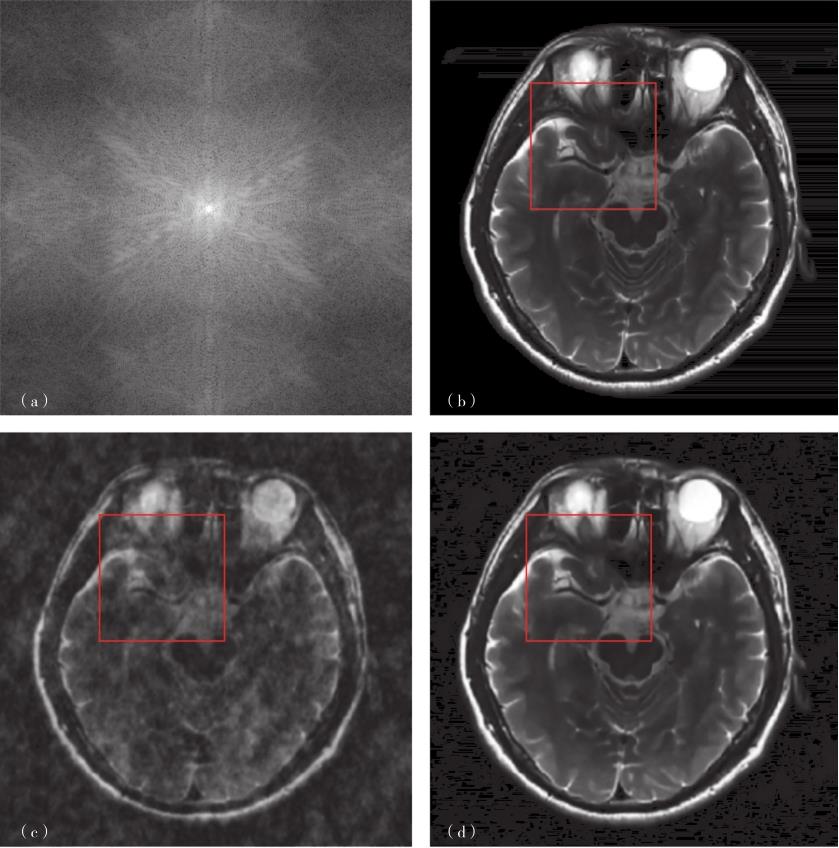

图3-1-4 基于稀疏字典的医学图像重建

(a)k空间信号;(b)原图;(c)欠采样0填充重建结果;(d)基于稀疏字典的重建结果;(e)测量矩阵;(f)是(b)的局部放大图;(g)是(c)的局部放大图;(h)是(d)的局部放大图。

还有一种使用单线圈进行欠采样重建的方式,即压缩感知(compressed sensing,CS)。奈奎斯特-香农采样定理告诉我们,在等步长采样的情况下,若想完整地重建原始信号,采样的点数应当足够多,其对应的采样频率应至少为原始信号中最高频率分量的两倍。压缩感知理论则告诉我们,如果信号在某个变换域中具有稀疏性,则可以使用更少的采样点来重建大部分原始信号。此时的采样方式也未必是等步长采样了。在压缩感知MRI中,最常见的一种采样方式是使用高斯采样矩阵进行采样[图3-1-4(e)]。另外,随着神经网络在图像重建中的不断应用,建立神经网络学习采样矩阵也受到一定关注。